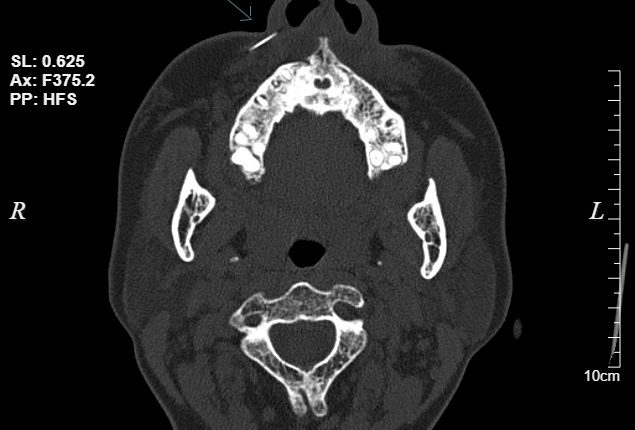

Sau khi thực hiện chụp CT, kết quả cho thấy hình ảnh dị vật khoảng 1cm vị trí phần mềm cánh mũi phải. “Vị trí kim găm sâu vào má, bệnh nhân được bác sĩ chỉ định thủ thuật lấy dị vật”. Sau 10 phút, dị vật là đầu kim đã lấy ra từ vùng má bệnh nhân.